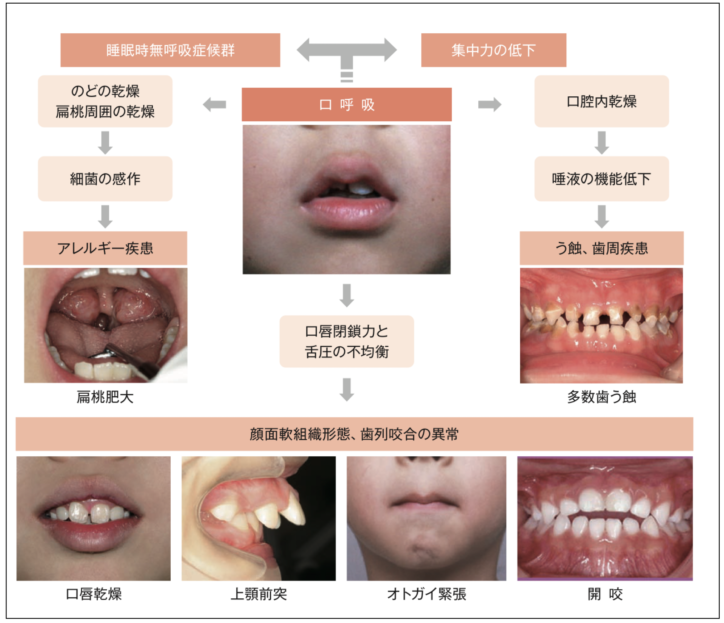

特に『お口ポカン・口呼吸』は以下のように様々な病気の重症化につながるリスクがあります。

お口を開いていることで虫歯や歯肉炎や歯並びなどのお口の問題だけでなく、アレルギーやアデノイドの肥大など様々な疾患を重症化させるリスクとなります。

つまり、お口をきちんと閉じるようにできるようになれば、口呼吸、鼻へい、気道閉塞、アレルギーなどを軽症化できる可能性もございます。

最近以下のような子ども達がとても多く増えてきてます。

①お口ポカン・口呼吸

②くちびる・前歯が使えない

③くちびるをすぼめることができない

④舌をうまく使えない

⑤舌を置く位置が分からない

⑥正しいつばの飲み方ができない

今回は①〜③のお口を閉じる力が弱いことが原因の一つである

『口唇閉鎖力不全症』〜何もしていない時(安静時)にお口が開いている状態〜

上記のように、お口を開いていることで、虫歯や歯肉炎や歯並びなどのお口の問題だけでなく、アレルギーやアデノイドの肥大など様々な疾患を重症化させるリスクとなります。

つまり、お口をきちんと閉じるようにできるようになれば、口呼吸、鼻へい、気道閉塞、アレルギーなどを軽症化できる可能性もございます。